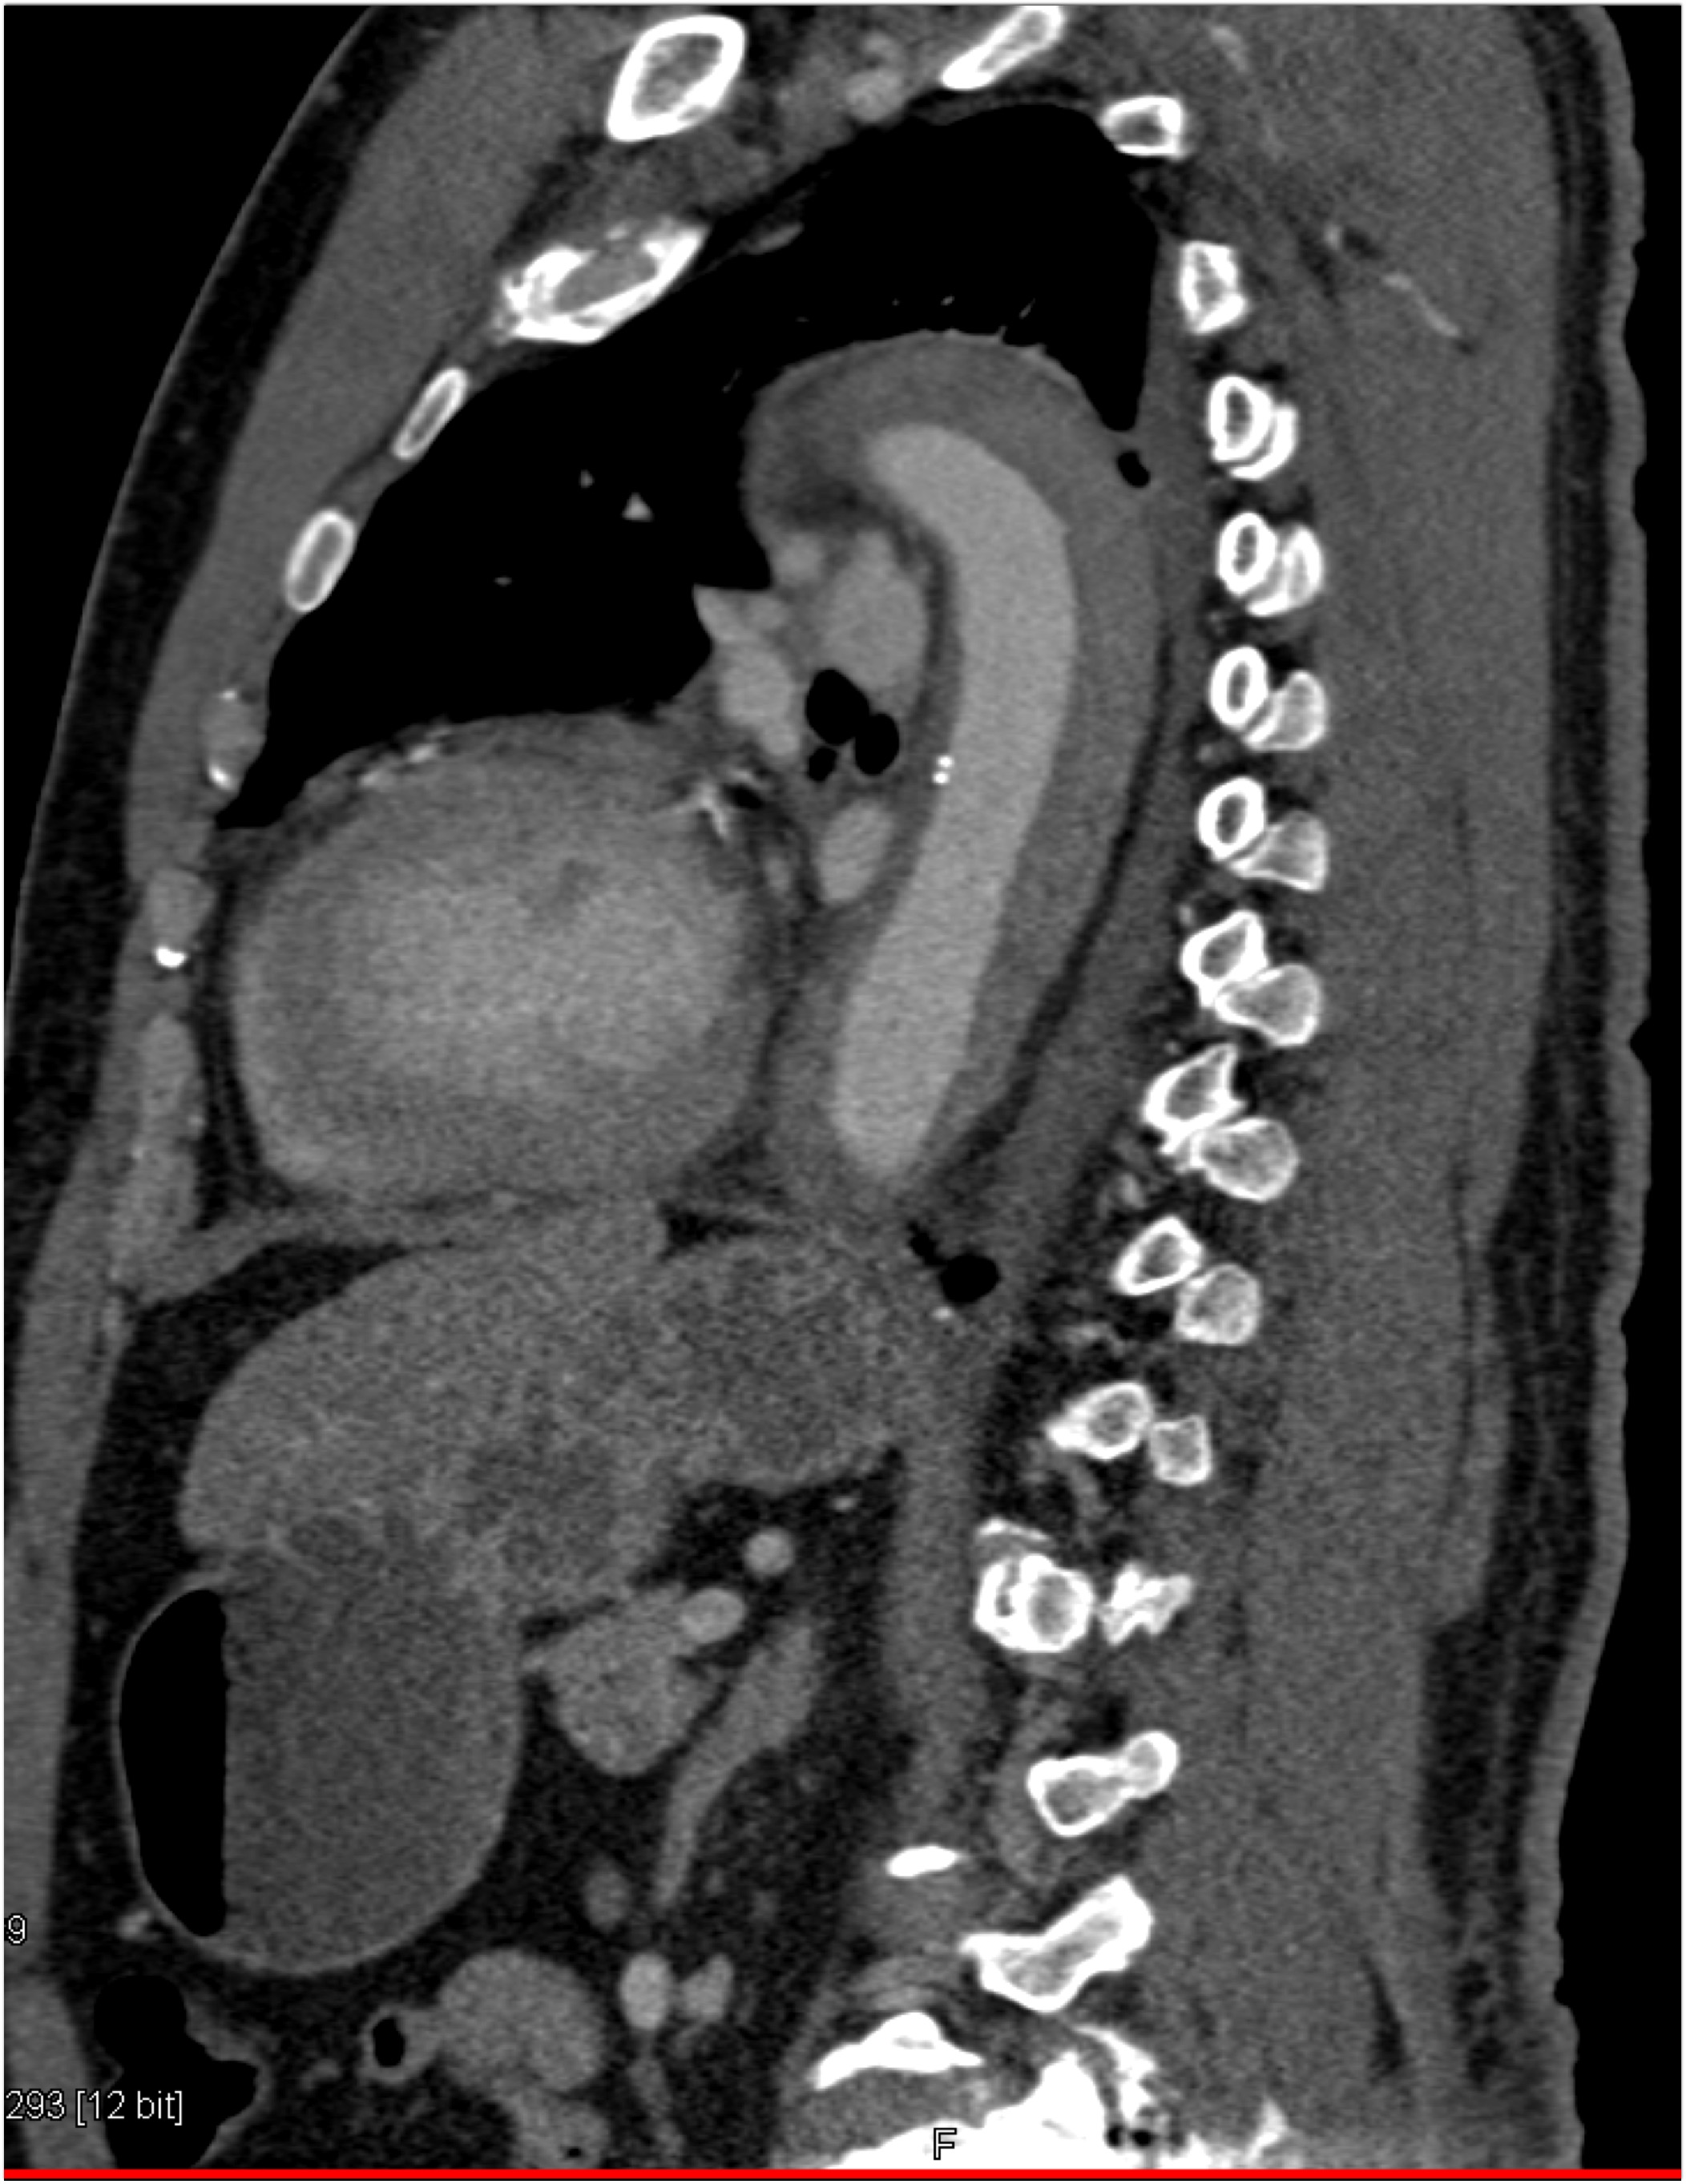

8) The most likely diagnosis in this case is?

clear cell renal cell carcinoma

large B-cell lymphoma

seminoma

renal abscess